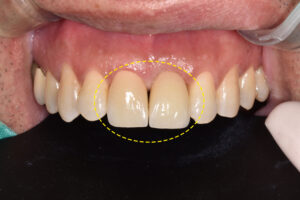

임플란트를 식립하고 지혈한 후,

임시치아까지 들어간 모습이에요.👏

옆에 재 크라운 치료를 진행할 치아도

함께 임시치아를 만들어 드렸는데요.

말 그대로 임시로 사용하는 치아지만

자연스럽게 제작되어 환자분께서도

만족하셨답니다😁

이제 이상태로 앞니 임플란트와

잇몸뼈가 단단히 유착되길 기다리게 되며,

약 3개월 후 최종 보철물을 제작했어요.

두 치아 모두 최종 보철물이 들어가고

치료가 마무리 되었어요.🦷

앞니 치료는 기능적으로도 중요하지만

심미적인 부분 역시 빼놓을 수 없는데요.

환자분께서는 당일 발치부터 식립, 임시치아까지

번거롭게 시간 내서 내원하지 않아도

한 번에 할 수 있을지 모르셨다며,

아무도 당일에 치아를 빼고 치료한 지 몰랐을 정도로

임시치아부터 본 보철물까지 심미적이라 매우 만족한다고

하시며 감사의 인사를 전해주셨어요.